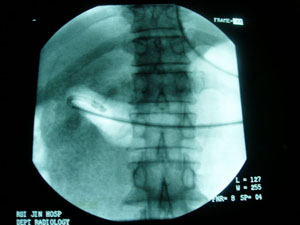

X線下放置螺旋胃管

由於重症SAP,胃癌患者通常存在胃腸麻痹,所以許多情況螺旋胃管無法自行到達空腸.故X線下放置螺旋胃管不失為一種好方法,研究發現: